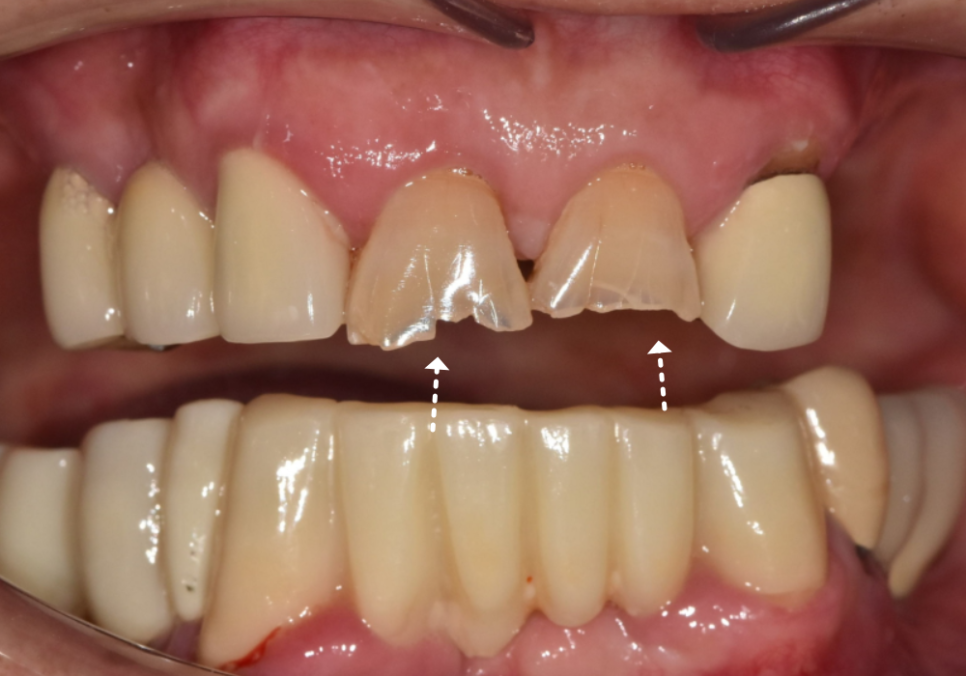

다행히 앞니(#11, 21)를

정밀하게 살펴본 결과

금이 치아 겉면에만

머물러 있는 상태였습니다.

신경이라는 예민한 통로까지는

손상되지 않아 신경치료 없이

크라운 치료로 진행하기로 했는데요.